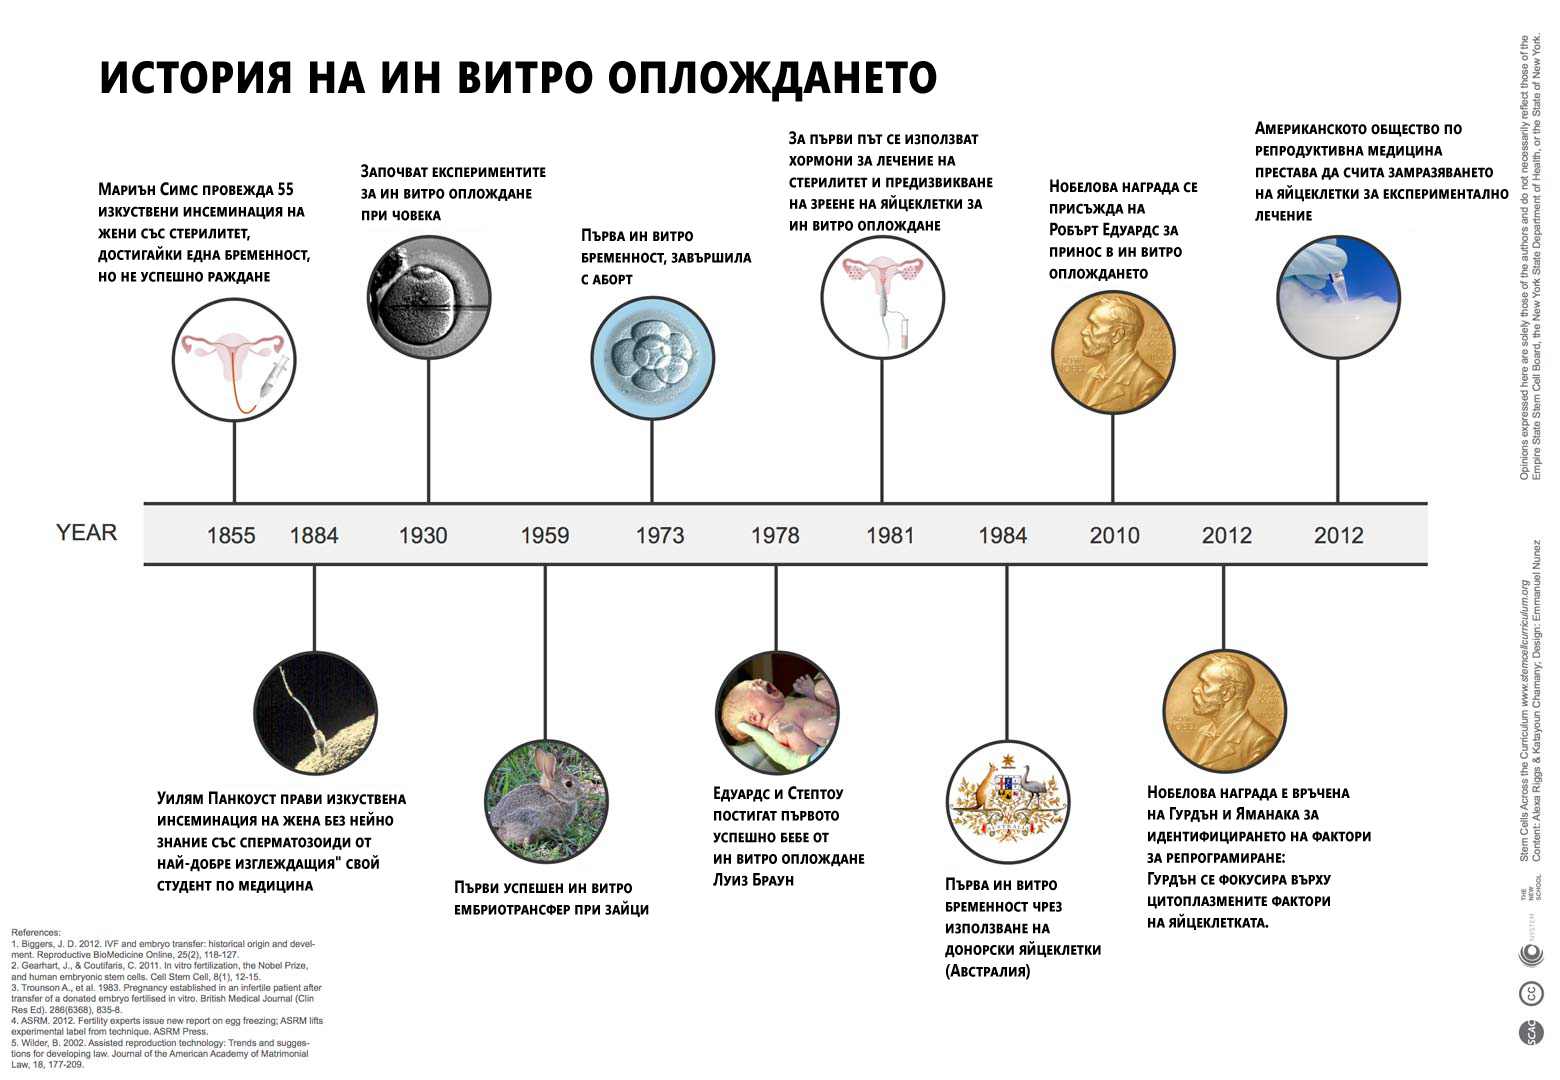

Това лечение позволява на двойки с различни репродуктивни проблеми да заченат, а в днешни дни помага и на еднополови двойки и самотни майки да имат деца. Технологичният напредък в репродуктивната сфера води до раждането на повече от пет милиона бебета според проучване от 2013 година. (Бел. ред. През 2017 вече са 6,5 милиона).

Но през 1978 година, лечението било експериментално. Д-р Макнами, директор на първата в света ин витро клиника “Борн хол” в Кембридж, вярва че Лиуз “е истинско чудо”.

Двамата мъже пионери в областта, гинекологът Партик Стептоу и носителят на нобелова награда физиолог Робърт Едуардс “са направили стотици ембрионални трансфери преди да успеят със зачеването на Луиз”, добавя той. Двамата обединяват усилията си цели 10 години по-рано. Те имат умения, които чудесно се допълват:

Едуардс има успехи в оплождането в лабораторни условия, а Стептоу разработва метод за извличане на яйцеклетки от яйчниците.

“Щом веднъж Стептоу и Едуардс успяват да оплодят яйцеклетка, те много бързо разбират, че трябва да ограничат броя получени ембриони за трансфер, за да намалят вероятността за многоплодна бременност”, обяснява Макнами. “Развитието на крио технологиите през 80те години довело до трансфер само на 1-2 ембриона и замразяването на останалите за бъдеща употреба. По този начин се спестява повторно извличане на яйцеклетки.”

Техниката за директно инжектиране на сперматозоид в яйцеклетката, разработена в края на 80те, е пробив в лечението на мъжкия стерилитет.

Тези, както и други по-малки, подобрения водят до постепенно повишаване на шансовете за зачеване при ин витро цикли. През 80те, когато първата работа на д-р Макнами била да смесва яйцеклетката със спрематозоидите в блюдо на Петри, успеваемостта е едва 10%, сега е около 40%.

Шансовете за зачеване чрез ин витро намаляват с напредването на възрастта, но процесът сега е по-успешен от естествено зачеване в даден цикъл. Но все още няма всеобощо одобрение.